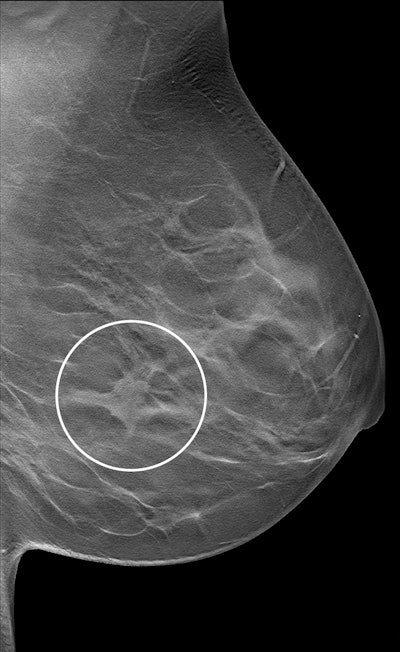

Imaging depicts a screen-detected invasive breast cancer in the dense breast tissue of a 59-year-old woman. A section in the mediolateral oblique view from a DBT exam of the left breast shows an irregular mass with surrounding architectural distortion (circle). The participant had no history of breast cancer and had been screened previously in the German mammography screening program. Histologic analysis showed invasive carcinoma of no special type, grade 2, with tumor size of 18 mm. Image courtesy of the RSNA.